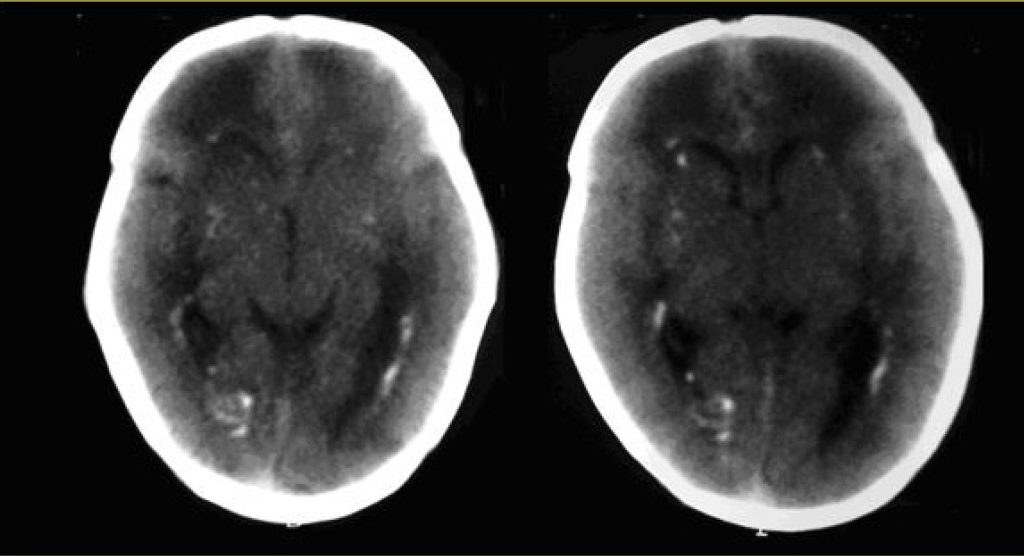

A female infant born at 37 weeks and 2 days of gestation by vaginal delivery was admitted to the neonatal intensive care unit on July 11, 2009 with birth weight of 2,030 g, height of 41,0 cm and head circumference of 31.0 cm. The infant Apgar were 8, 9 and 9 at 1, 5 and 10 min, respectively. A diagnosis of congenital toxoplasmosis was entertained because of the mother clinical history (she IgG positive and IgM positive for toxoplasmosis with avidity of 85% during first trimester of pregnancy). At the first trimester morphology scan intracranial calcifications were seen. The newborn had intrauterine growth restriction, splenomegaly, petechias and thrombocytopenia. Treatment of toxoplasmosis was done with sulphadiazine, pyrimethamine and folinic acid. The tomography of the skull showed multiple foci of bilateral periventricular calcifications and on the base nuclei. Due to these findings the serology for cytomegalovirus of mother and child was ordered. The mother was IgM negative, but IgG positive. The newborn was IgM and IgG positive. Cytomegalic inclusions in newborn’s urine and polymerase chain reaction (PCR) for CMV had positive results. The newborn was discharged and was referred to outpatient clinic to be treated with ganciclovir.

The congenital infections, syphilis, toxoplamosis, rubella, cytomegalovirus and herpes correspond to the acronym STORCH, and are characterized by common symptoms as: intrauterine growth restriction, hepatosplenomegaly, jaundice with increased direct bilirubin, anemia, petechiae, skin and mucosa lesions, encephalitis, pneumonia and thrombocytopenia(,). To diagnosis STORCH the most common methods are serological research of IgM and IgG, PCR and imaging exams. The clinical picture of toxoplamosis mainly shows hydrocephalus or microcephaly, diffuse cerebral calcifications in cerebral cortex, microphthalmia and chorioretinitis (due to microcephaly)(). The cytomegalovirus causes periventricular calcifications, and in ophthalmoscopy the chorioretinitis is not associated to microphthalmia. Herpes is identified when maternal genital herpes is diagnosed.